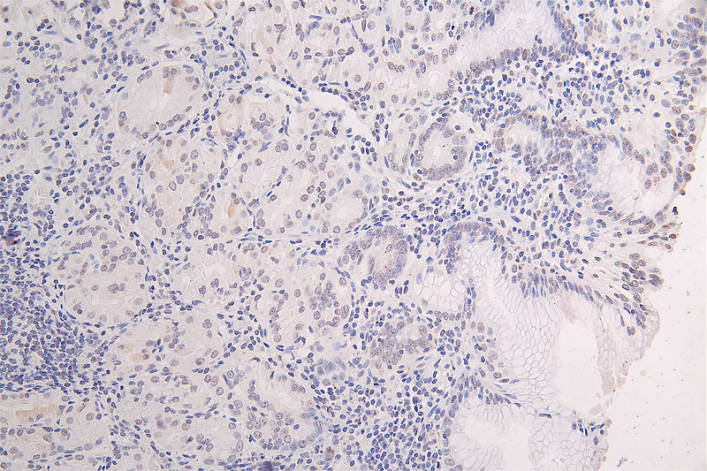

IHC image of CSB-RA051594A0HU diluted at 1:50 and staining in paraffin-embedded human brain tissue performed on a Leica BondTM system. After dewaxing and hydration, antigen retrieval was mediated by high pressure in a citrate buffer (pH 6.0). Section was blocked with 10% normal goat serum 30min at RT. Then primary antibody (1% BSA) was incubated at 4°C overnight. The primary is detected by a Goat anti-rabbit polymer IgG labeled by HRP and visualized using 0.10% DAB.